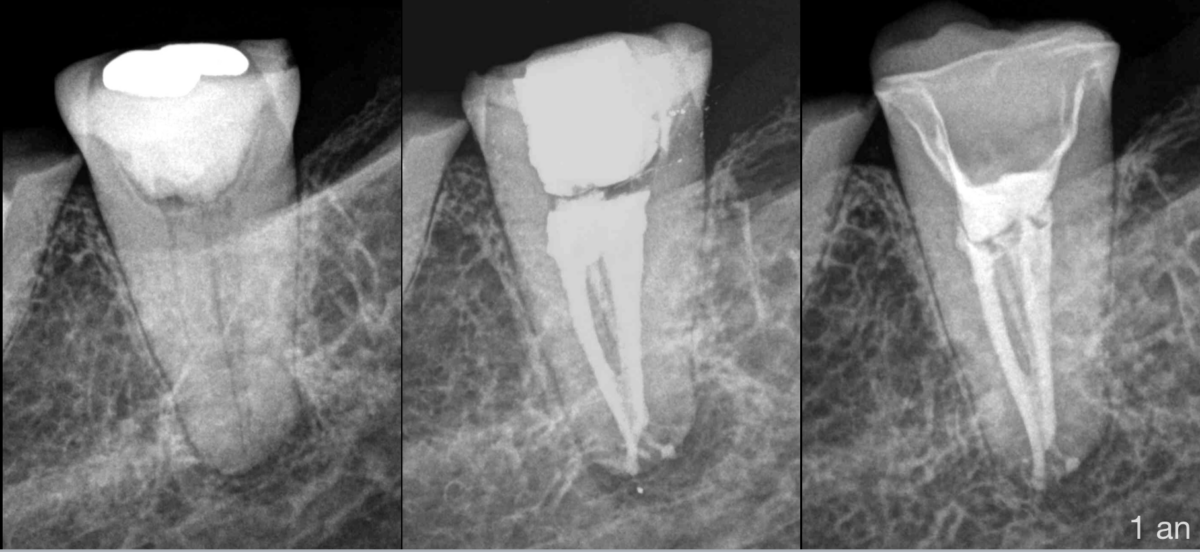

✨ 𝐀̀ 𝟏 𝐚𝐧 𝐝𝐮 𝐭𝐫𝐚𝐢𝐭𝐞𝐦𝐞𝐧𝐭, 𝐥𝐚 𝐜𝐢𝐜𝐚𝐭𝐫𝐢𝐬𝐚𝐭𝐢𝐨𝐧 𝐞𝐬𝐭 𝐞𝐟𝐟𝐢𝐜𝐚𝐜𝐞. ✨

Le patient nous demande si « c’est bon, c’est gagné pour toute la vie » ?

✅ 𝐐𝐮𝐞 𝐥’𝐨𝐧 𝐬’𝐞𝐬𝐭 𝐦𝐢𝐬 𝐝𝐚𝐧𝐬 𝐥𝐞𝐬 𝐦𝐞𝐢𝐥𝐥𝐞𝐮𝐫𝐞𝐬 𝐜𝐨𝐧𝐝𝐢𝐭𝐢𝐨𝐧𝐬, 𝐩𝐨𝐮𝐫 𝐪𝐮𝐞 𝐥𝐞𝐬 𝐜𝐡𝐨𝐬𝐞𝐬 𝐬𝐞 𝐩𝐚𝐬𝐬𝐞𝐧𝐭 𝐛𝐢𝐞𝐧 𝐩𝐞𝐧𝐝𝐚𝐧𝐭 𝐥𝐞 𝐦𝐚𝐱𝐢𝐦𝐮𝐦 𝐝’𝐚𝐧𝐧𝐞́𝐞𝐬.